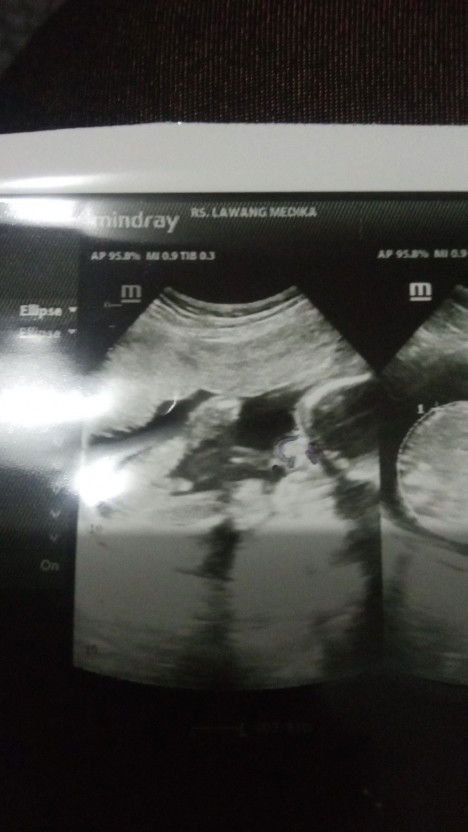

Bundaa.... Kemarin habis periksa ke bidan, dilihat dr TFU besar janinnya sudah cukup, disuruh kontrol makanan yg mengandung karbo sama gula, dan hari ini saya coba USG untuk memastikan BBJ berapa, dan ternyata BBJ baru 2 kg dg UK 34 minggu, Saya bingung bund, harus nambahin makannya atau kurangi makannya ya bund? Takutnya hasil USG gak akurat, saya baca beberapa postingan bunda banyak yg berat lahir lebih kecil dr hasil USG... Share pengalaman nya dong bund, minta sarannya... #bantusharing